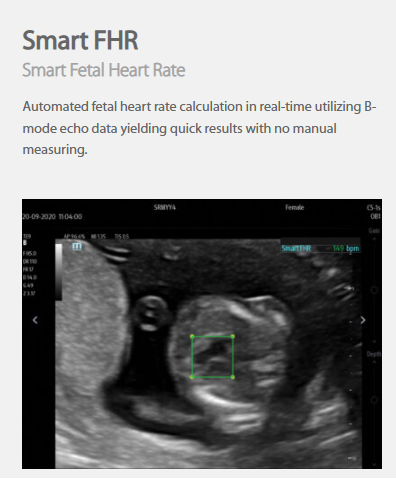

The technology-rich TE X Ultrasound System gives clinicians access to market-leading artificial intelligence (AI)-powered Smart Tools, an ergonomically designed system, and proprietary software-based beamformer Zone Sonography Technology+ (ZST+). By incorporating these elements, the TE X Ultrasound System provides access to advanced diagnostic data, the ability to adapt to the various clinical scenarios at point of care, and best-in-class imaging to help them provide a higher standard of care.